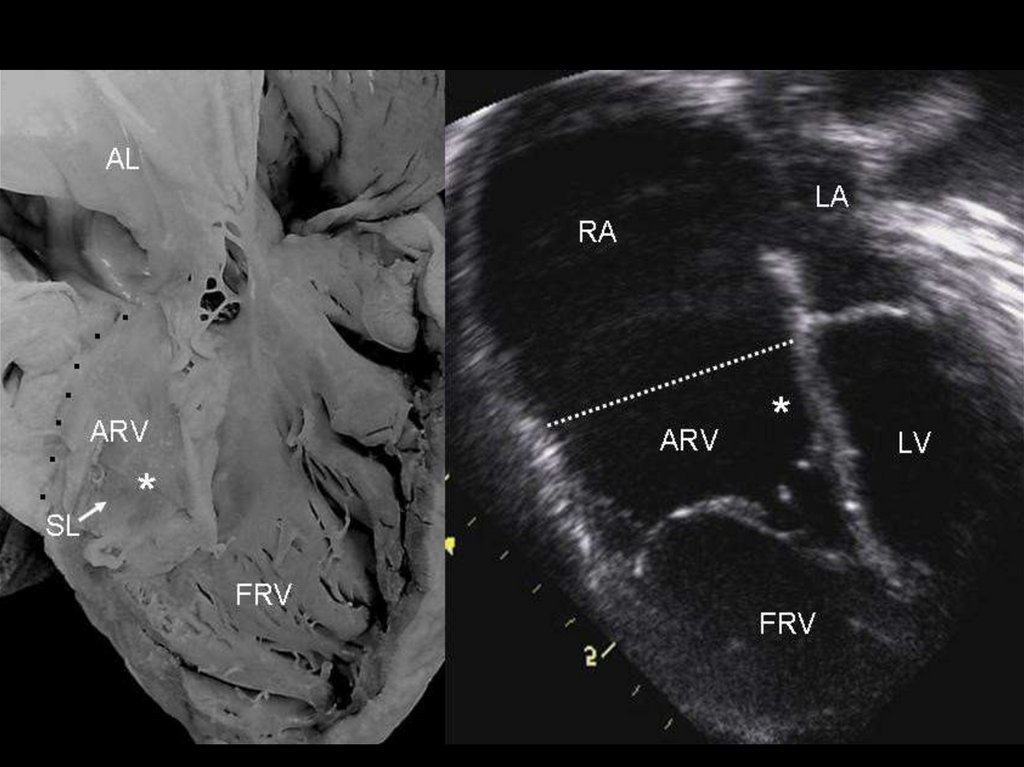

ЭхоКГ

Метод четко выявляет аномалию, однако существуют специфические черты, на которые

следует обратить особое внимание:

точная оценка створок трикуспидального клапана, их прикрепления и степени регургитации;

целостность межпредсердной перегородки;

целостность МЖП;

оценка размера ПЖ;

проходимость и размер выходного отдела ПЖ и ветвей ЛА;

проходимость артериального протока;

исключение аномалий левой половины сердца.